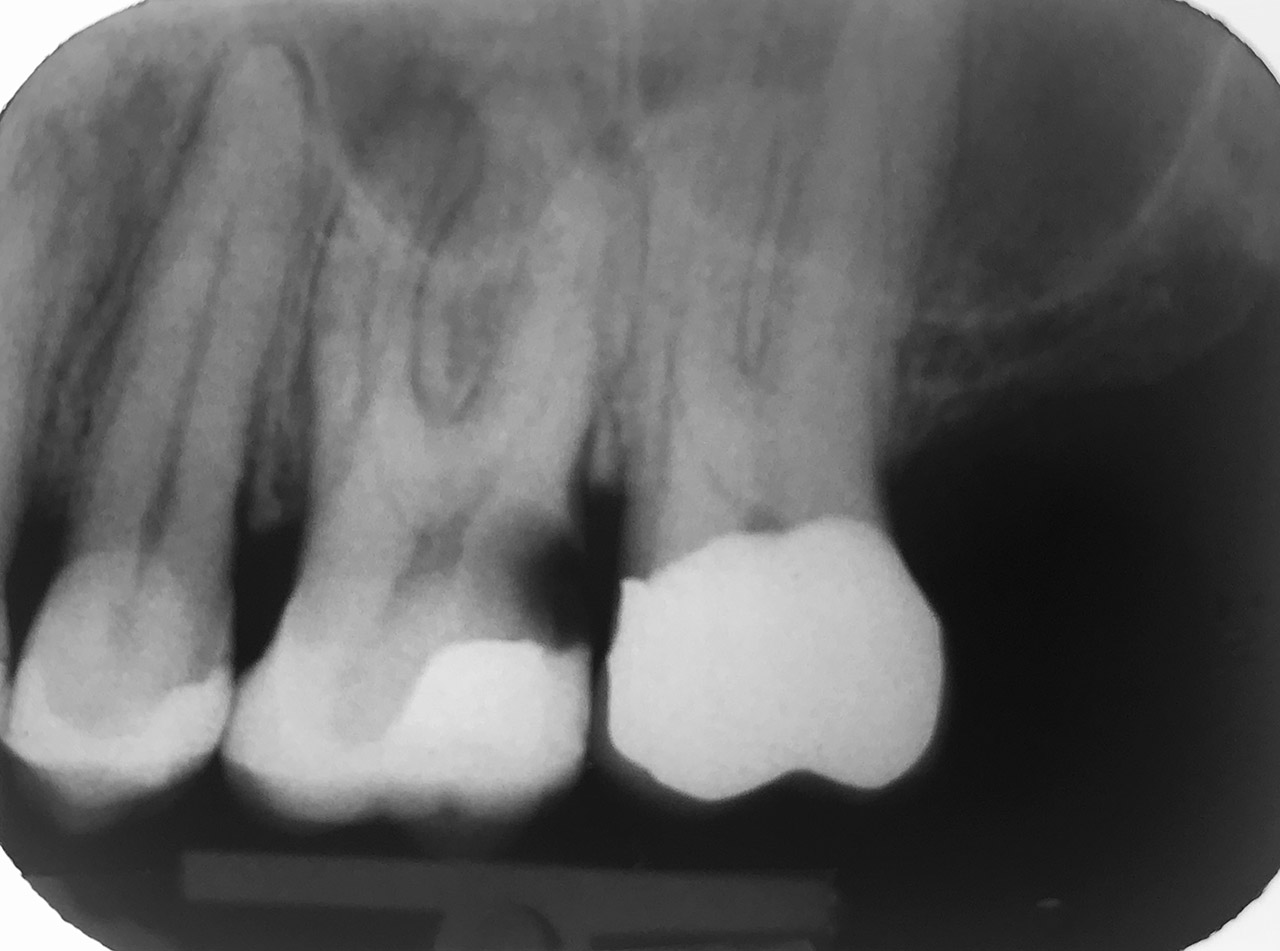

Wurzelbehandlung/Endodontie:

Massiver Paro-/Endodefekt bei den Zähnen 38&37. Extraktion von 38 (Weisheitszahn) und Wurzelbehandlung von 37 (4 Kanäle). Defekt vollständig ausgeheilt.